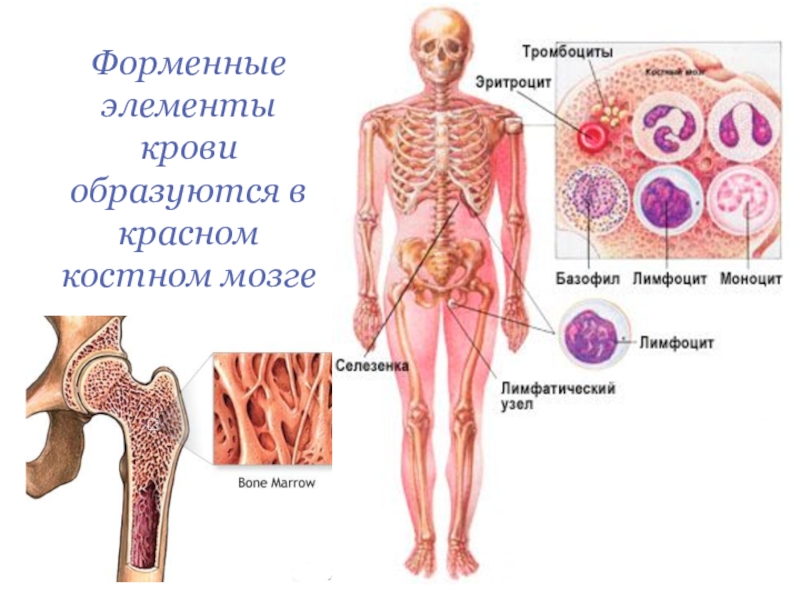

Изучение костного мозга: анатомия и функции